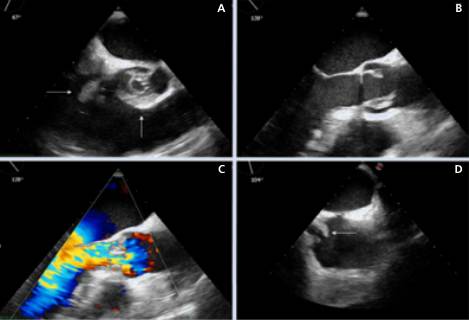

Fig. 3

Ecocardiograma transesofágico. En la imagen A se aprecia una vista axial a nivel de los grandes vasos basal, con compromiso valvular aórtico (flecha vertical) que impide su correcto cierre y se aprecia la proyección ventricular de una vegetación de la valva septal tricuspídea (flecha horizontal). En la imagen B se aprecia una vista longitudinal del tracto de salida del ventrículo izquierdo, dos vegetaciones en válvula aórtica. En la imagen C se aprecia el Doppler color de la imagen previa, en la que se puede observar un flujo regurgitante aórtico en diástole. En la imagen D se aprecia una vista bicava levemente rotada en la que se aprecia una vegetación (flecha horizontal) sobre la desembocadura de la vena cava inferior, compatible con vegetación de la red de Chiari.